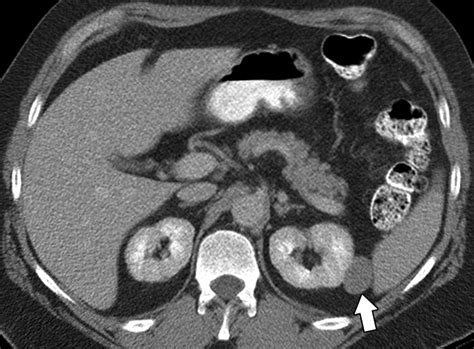

Imaging tests, such as CT scans, MRI, and PET scans, are commonly used to determine the stage of kidney carcinoma. These tests provide detailed images of the tumor and surrounding tissues, helping to assess the extent of the disease.